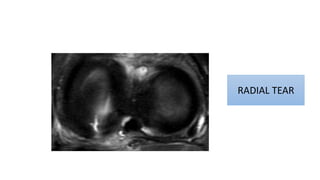

RADIAL TEAR